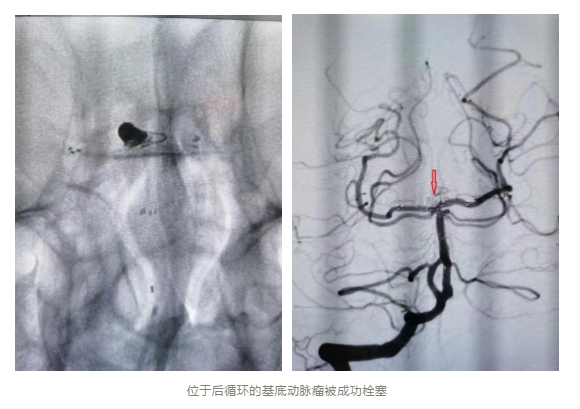

在脑血管造影中可以看到该动脉瘤位于基底动脉远端,且瘤颈宽,动脉瘤基底部累及双侧大脑后动脉。此动脉为大脑的重要供血血管,若该动脉不幸被栓塞住,则会造成严重的大脑缺血症状,使患者陷入昏迷甚至死亡。李成林主任表示,该手术难度在于要成功栓塞动脉瘤的同时,保证双侧大脑后动脉的血液循环通畅,意味着这个介入栓塞手术难度比一般动脉瘤更高。获得家属同意后,李成林主任带领团队为其介入治疗,该团队在介入栓塞手术上具有扎实的理论知识和丰富的实践经验,在Y型支架辅助下,成功地栓塞住基底动脉瘤,周围血管状况良好。